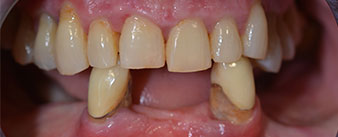

La patiente âgée de 64 ans présente une denture résiduelle des dents 38, 33 et 43 et une prothèse amovible mandibulaire stabilisée par crochets (Fig. 1 et 2).